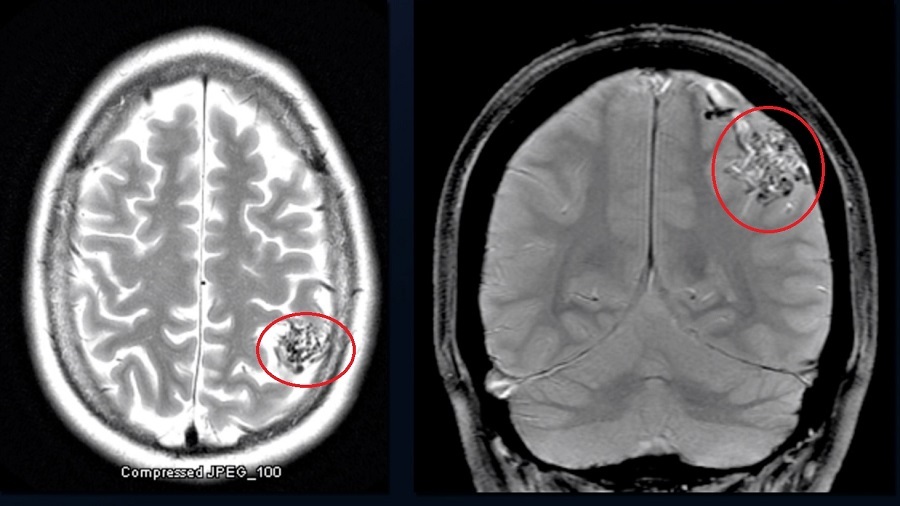

cerebral AVM

tangle of connected arteries & veins

can cause bleed, seizures, headaches, ischemic stroke (steal phenomenon)

bag of worms appearance on MRI

requires angiography for diagnosis

resection can be curative